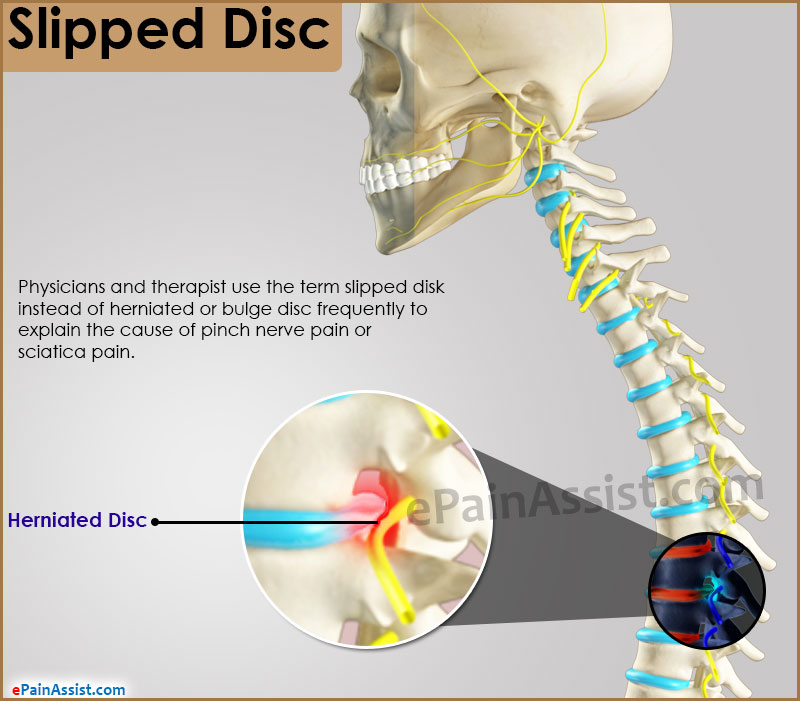

Bulging and Slipped Disc Symptoms

My Slipped Disc

Slipped Disc | Spine health, Cluster headaches, Back care